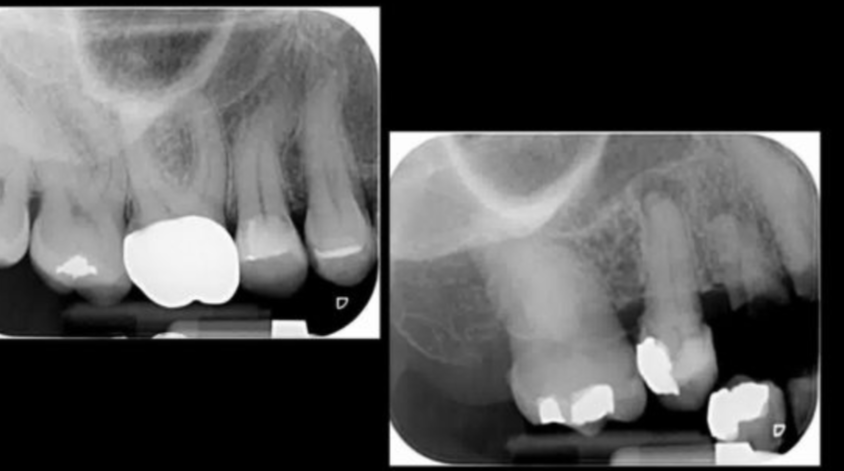

is the following periapical pathology or not?

yes

83

yes - root filled - PDL isnt continuous - lamina dura isnt continuous

no

85

86

yes - it is crowned - apical radiolucency - lamina dura tracking off